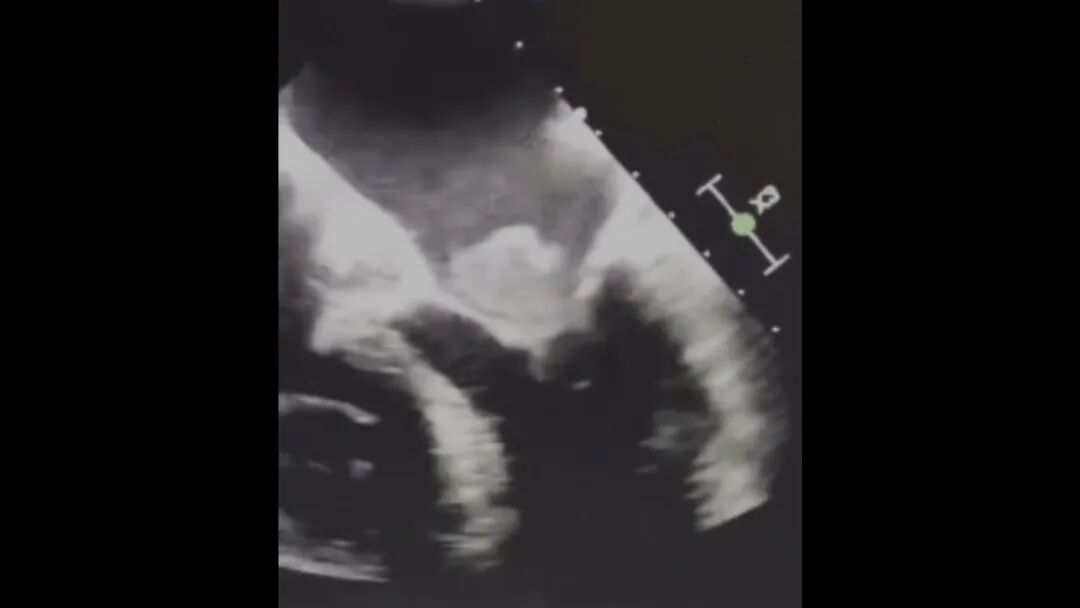

跳动 漂浮血栓 肺栓塞

有种异物竟可能随着心脏“跳动”!如果没有及时发现可能迅速致命!这个异物到底是什么?它又是从哪来的?为什么会跑到心脏里面去呢?更多精彩内容,敬请关注本期《养生堂》。

专家揭秘,这个异物就是“漂浮血栓”,它和我们熟悉的血栓相比有什么区别?为什么它更加高危?我们如何提前发现它的蛛丝马迹?更多精彩内容,敬请关注本期《养生堂》。